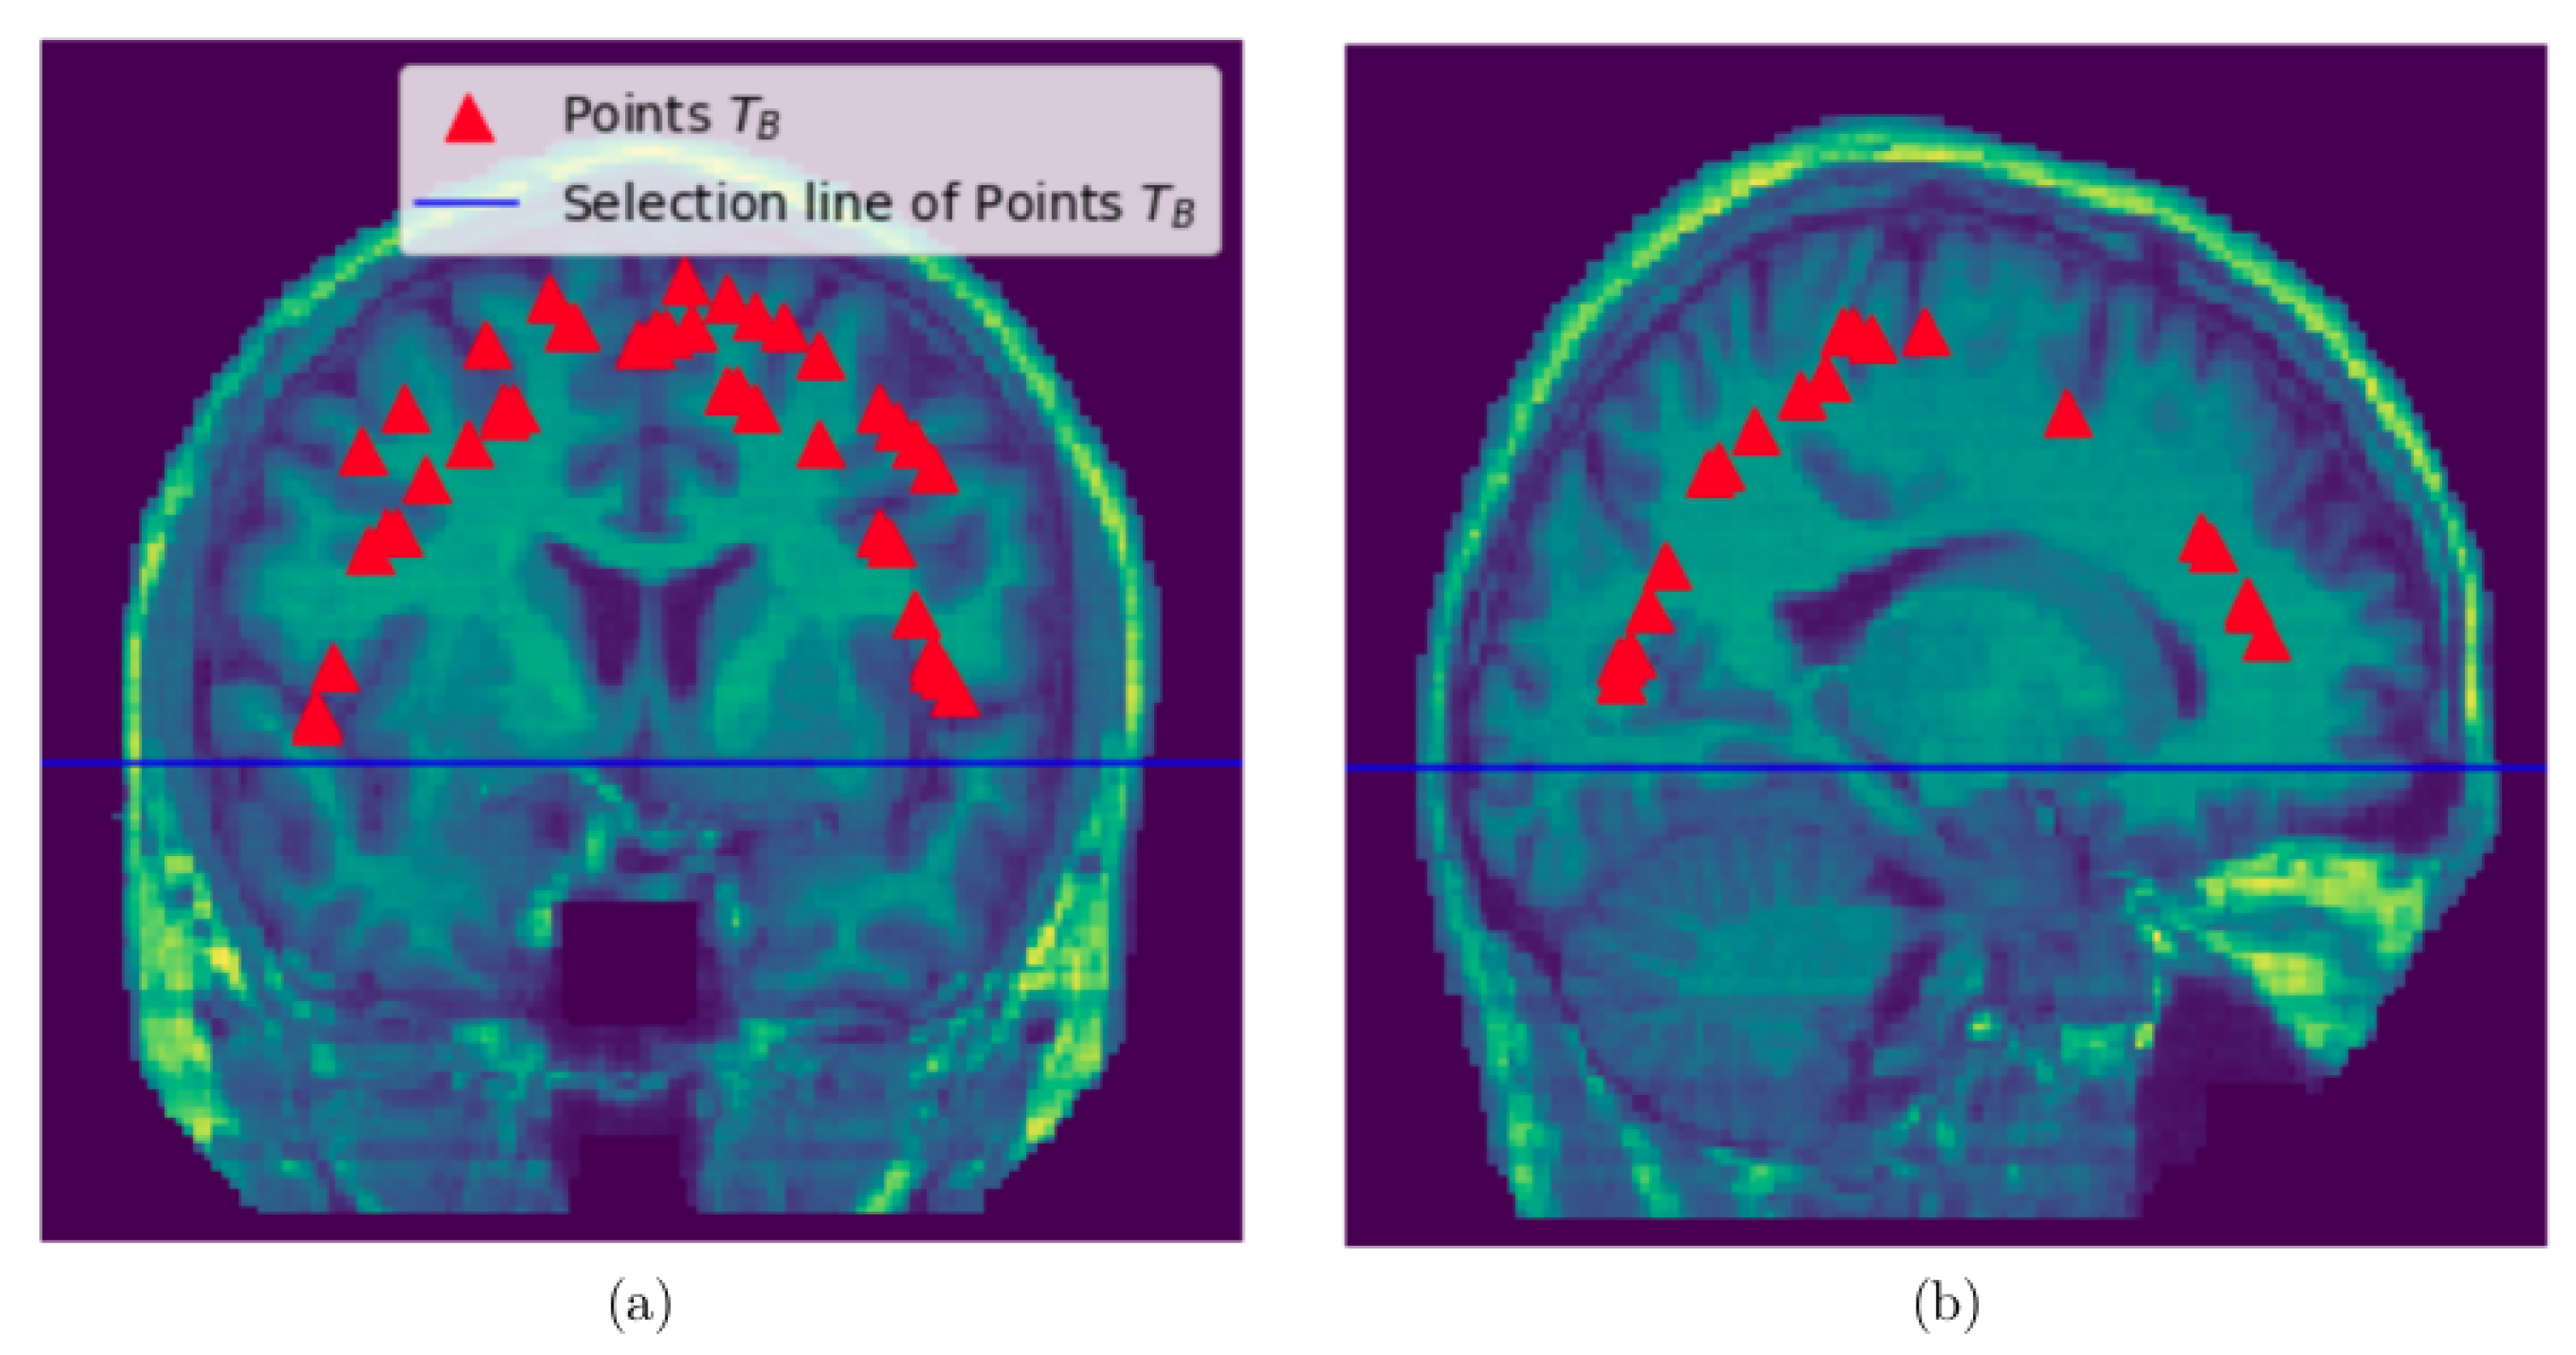

We do the following things to obtain points in : From the discrete 3D edge-like points distributed at the surface of the head we take points above the selection line which is obtained by visual inspection (see Figure 3). Then, pull these points from the surface of the head to the brain by a certain distance . Then, compute the mean point of the pulled points. For each pulled point a distance is computed from the mean point and get the maximum distance. Then, the maximum value times 0.75 is the a distance threshold value for removing the points with the distance above the threshold value. This last step is performed to restrict the pulled points to lie within the brain and remove points close to the skull.

Figure 3.

Sampling points within the brain: (a) Sampled slice coronal section showing the selection line and points sampled within the brain, (b) Sampled slice sagittal section section showing the selection line and points sampled within the brain.